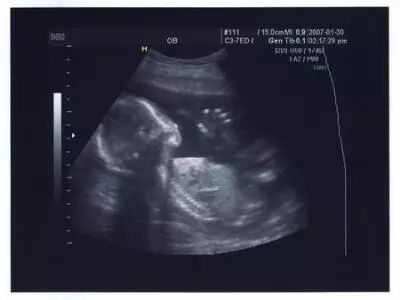

2. 男性胎儿会在母亲子宫里勃起

医学研究发现,男女婴儿在子宫内都可能产生手淫的举措。超声波图像曾抓拍到男婴的勃起图片,不过由于生殖器官差异的原因,只有男性能在X光片上看出来。